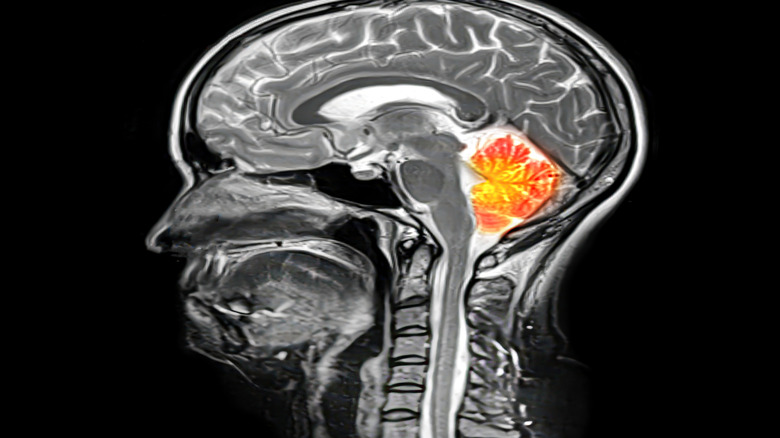

The cerebellum is crucial for long-term memory

The cerebellum, meaning "little brain," is known to be the part of your brain responsible for movement and motor skills. However, recent research has shown that it is not only in charge of the motor function you carry out in the present tense, but also for the long-term memory of those motor skills.

For a long time, scientists have understood that damage to the cerebellum can cause issues with balance, muscle coordination, and vision, but the most recent research found that patients were able to learn new motor skills when they were able to practice them shortly afterward. The more time that passed between practicing the skill, the more likely it was that it would be forgotten. This suggests that a key function of the cerebellum is taking short-term learning and turning it into a long-lasting skill. It should be noted, though, that the term "long-lasting" used in this study doesn't refer to months or years: The difference between a 10-second interval and a 60-second interval was enough to see a dramatic change in the participants who had cerebellum damage, showing how critical this tiny part of the brain is to committing a fleeting moment to a more permanent feature.